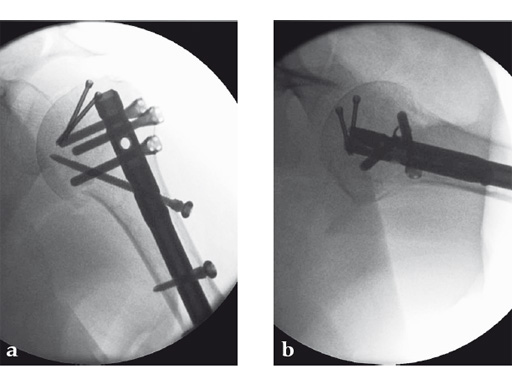

Following a fall downstairs, a 70-year-old woman sustained a head injury with intracerebral and subdural haematoma, as well as a complex fracture of the right humerus, representing a minimal displaced proximal and an oblique fracture in the distal part of the humerus (Fig 11).

After neurosurgical intervention, surgery of the humerus was planned 10 days after the index trauma. The patient was still at the neurological intensive care unit and a preoperative clinical examination of the patient, regarding radial nerve palsy, was not possible. Therefore, a surgical revision with exploration of the radial nerve and an osteosythesis of the humerus using a long MultiLoc Humeral Nail was indicated.

The patient was operated on in beach chair position. For the exploration of the radial nerve, a limited anterolateral approach was used. The nerve was mobilized and retracted laterally. An anterolateral approach to the proximal humerus was performed. The supraspinatus showed a small acute rupture without retraction. The supraspinatus tendon was split to get access to the insertion area on the humeral head. A 270 mm long MultiLoc Humeral Nail of 8.5 mm diameter was inserted under visual and x-ray control to the desired endpoint. Reduction of both the proximal and the distal humerus fracture was anatomical. In the lateral view there was a small gap, and it was decided to apply compression after distal locking (Fig 12). Proximally, three MultiLoc screws were inserted and a 2 mm end cap was placed. Finally, the supraspinatus rupture was reconstructed with transosseous sutures and secured with an augmentation plate. The posterior greater tuberosity fracture was secured with Fiber Wire to the MultiLoc screws. Fig 13 illustrates the definitive fixation.